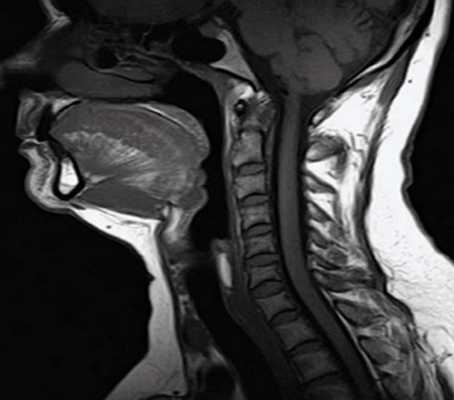

Особенностью МРТ являлась высокая контрастность мягких тканей. Плотные костные ткани или зубоврачебный материал не создавали артефактов, что давало возможность получать четкое изображение опухоли полости рта, определять распространение в мягкие ткани, глубокие отделы орофарингеальной зоны, в область неба. На Т1-ВИ все опухоли имели ту же интенсивность сигнала, как у окружающих мышц или слабее (рис.7).

Рис.7. Пациент С., 55 лет. МРТ ротоглотки в сагиттальной проекции в режиме Т1-ВИ. Опухоль дна полости рта с переходом на нижнюю поверхность языка (стрелки)

После введения контрастного вещества все опухоли показывали усиление сигнала. При локализации опухолевого процесса в области языка (12 пациентов) границы опухоли визуализировались более четко. В режиме Т2-ВИ опухолевые узлы проявлялись более высокой интенсивностью сигнала, чем у окружающих мышц (рис. 8).